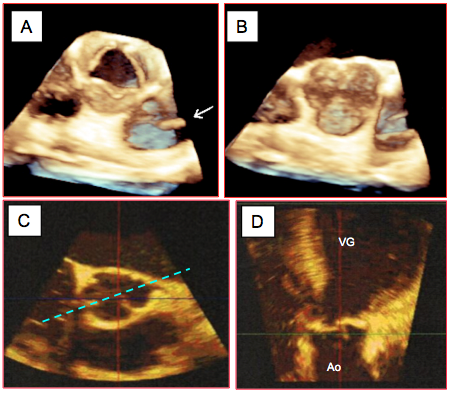

Figure 26.68 : Les différents types anatomo-pathologiques d’insuffisance aortique. A : maladie annulo-ectasiante ; la racine de l’aorte ascendante et l’anneau valvulaire sont dilatés (flèches rouges), mais les cuspides sont normales (IA type I) ; le jet de l’IA est central. B : la racine de l’aorte est normale mais les cuspides sont lésées ; elles peuvent être prolabantes (IA type II) ou rétractées (IA type III). Le jet de l’IA est en général excentrique ; il est dirigé à l’opposé de la cuspide prolabante ou du côté de la cuspide rétractée.